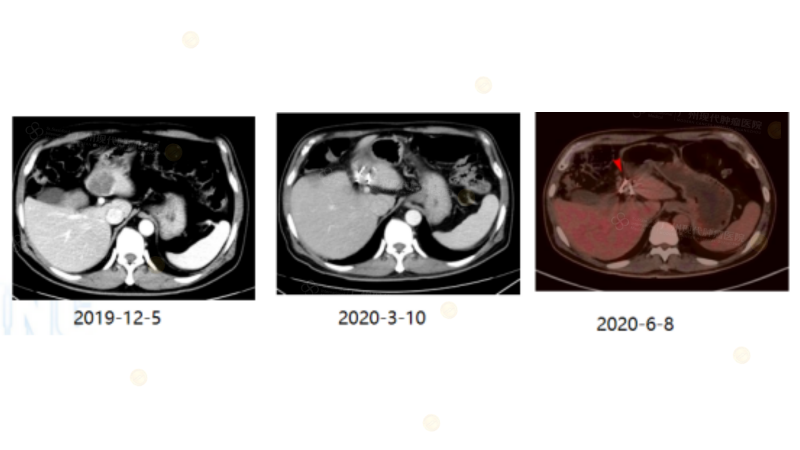

Case2

(注:2019年直肠癌患者,生物治疗后肺转移病灶CR,后续出现新发肝脏转移灶,考虑患者存在继发耐药,给予行局部碘-125 粒子植入治疗,为患者争取NED。)